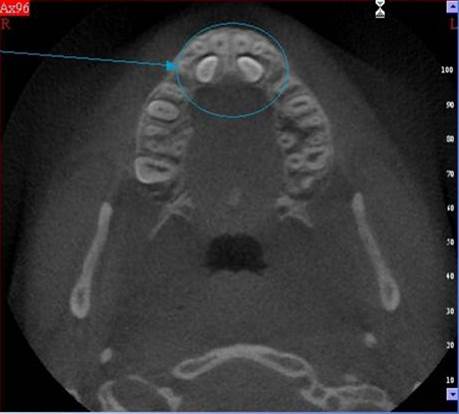

NewTom Giano

Jedná se o nejnovějším přístroj ze skupiny dentálních hybridních CBCT (3D) + 2D (pan i ceph) systémů. Opět umožňuje na základě jediného snímkování vytvořit všechny typy RTG zobrazení, které jsou pro lékaře potřebné. Používaná technologii tzv. „kuželového paprsku“ a speciální senzory pro minimální zátěž při snímkování pacienta.

Vyšetření pomocí tohoto přístroje (nebo

3D DVT - NewTom) a získaná data používáme

pro každou implantaci, dále ve stomatochirurgii (zlomeniny čelistí, zuby moudrosti, cysty, onemocnění čelistního kloubu), ortodoncii (retinované zuby, nadpočetné zuby), parodontologii atd.